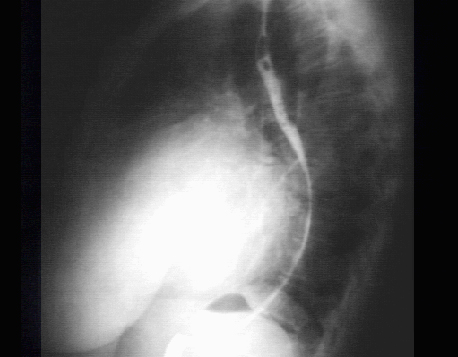

Lateral

The lateral view with barium swallow, demonstrates marked posterior displacement of the esophagus by the giant left atrium.